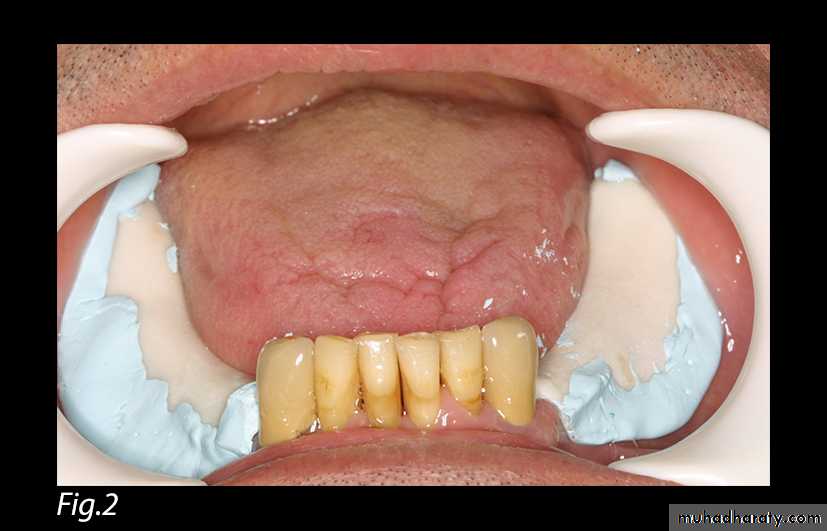

Fig. 2: Impression of the edentulous ridges without any compression.

The construction of a removable partial denture in distal extension cases is a delicate procedure since the prosthesis is supported by two different tissues, namely teeth and mucosa. The different resiliency of these supporting tissues may lead to the instability of the prosthesis. This paper describes a functional impression technique that aims to equalize the masticatory load between teeth and edentulous areas thus reducing the instability of the partial denture during function and preserving the residual teeth.Keywords: Distal extension - dental impression - removable partial denture.Procedure:1. An individual resin tray is constructed with the self-curing acrylic resin (Formatray; Sybron/Kerr Co, Romulus, Mich) on the edentulous ridges areas of a preliminary cast. Compound occlusal rims (Impression Compound, Kerr (Europe) Co AG CH-4051 Basel) are fixed on the outer surface of the individual tray. Care is taken so that the height of the occlusal rims surpasses the height of the residual teeth in order to ensure a positive and sole contact between the occlusal rims and the impression stock tray later on during the pick-up impression phase (Fig. 1). The tray is selectively relieved and covers the edentulous areas up to the border tissue attachment including the retromolar pads [3, 8, 10, 11].2. The individual tray is loaded with zinc oxide-eugenol impression paste (Cavex Outline by Cavex Holland BV) and brought to position without any compression while the soft tissues are left in their passive state (Fig. 2).Fig. 1: Individual tray with occlusal rims surpassing the height of residual teeth.